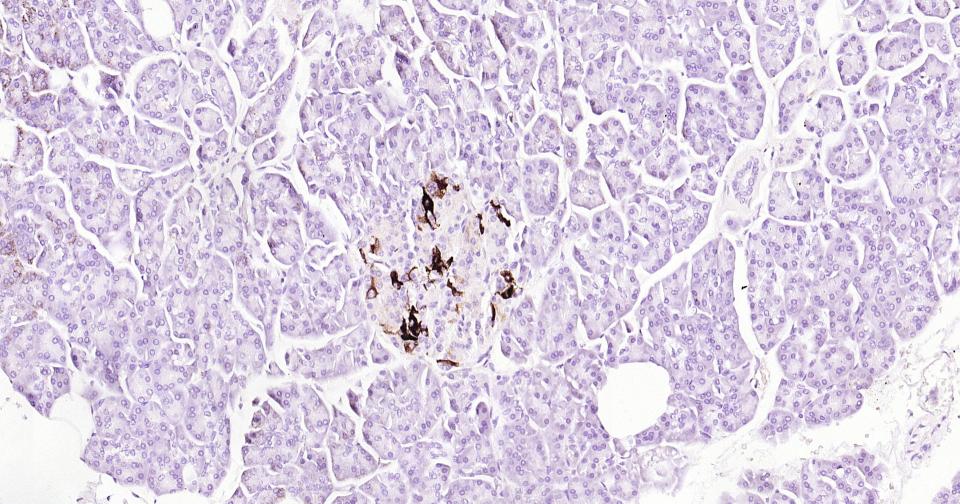

Paraformaldehyde-fixed, paraffin embedded Human Pancreas; Antigen retrieval by boiling in sodium citrate buffer (pH6.0) for 15 min; Antibody incubation with Osteopontin? Monoclonal Antibody, Unconjugated(bsm-43600R) at 1:200 overnight at 4°C, followed by conjugation to the SP Kit (Rabbit, SP-0023)and DAB (C-0010) staining.